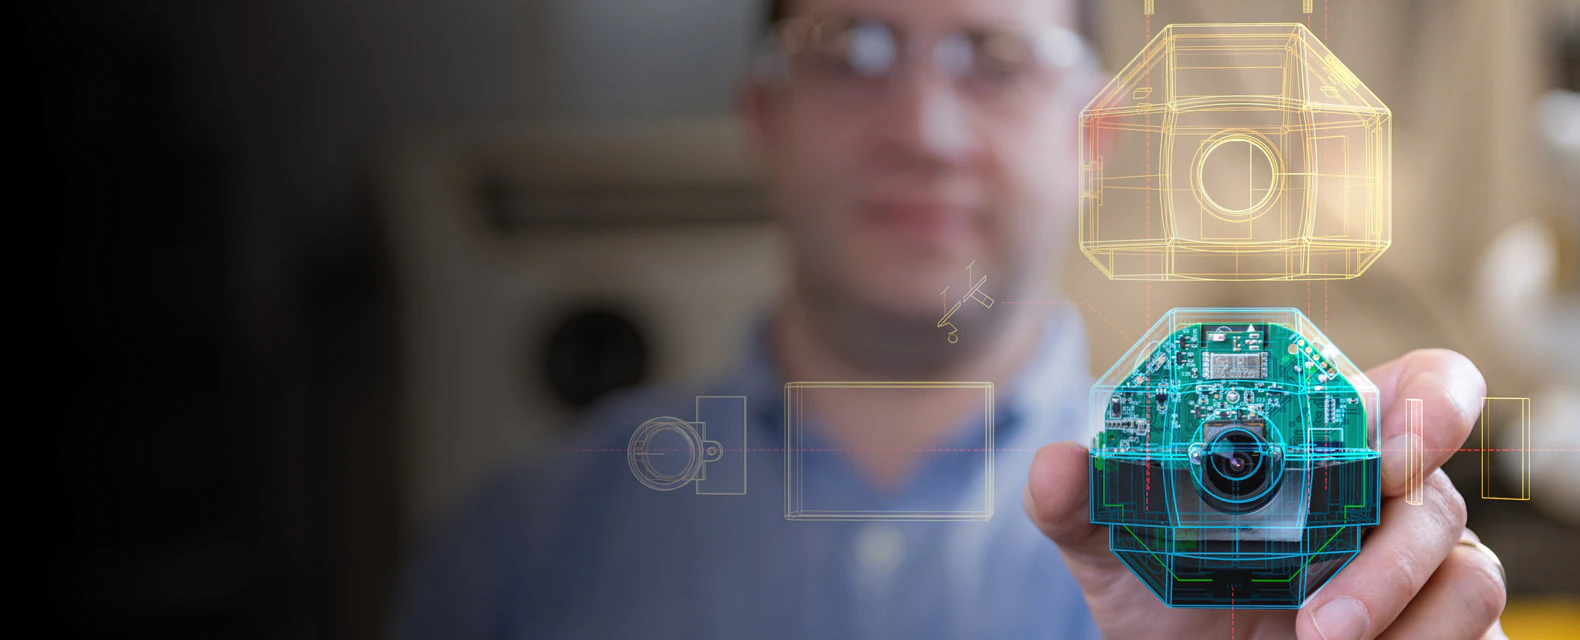

ARTICLE - Biosymbiotic, personalized, and digitally manufactured wireless devices for indefinite collection of high-fidelity biosignals

By TUCKER STUART, KEVIN ALBERT KASPER, CHRISTIAN IWERUNMOR, DYLAN THOMAS MCGUIRE, ROBERTO PERALTA, JESSICA HANNA, MEGAN JOHNSON, MAX FARLEY, THOMAS LAMANTIA, PAUL UDORVICH and PHILIPP GUTRUF | Science Advances | VOL. 7, NO. 41 | Oct 8, 2021

Digital medicine, the ability to stream continuous information from the body to gain insight into health status, manage disease, and predict onset health problems, is only gradually developing. Key technological hurdles that slow the proliferation of this approach are means by which clinical grade biosignals are continuously obtained without frequent user interaction. To overcome these hurdles, solutions in power supply and interface strategies that maintain high-fidelity readouts chronically are critical. This work introduces a previously unexplored class of devices that overcomes the limitations using digital manufacturing to tailor geometry, mechanics, electromagnetics, electronics, and fluidics to create unique personalized devices optimized to the wearer. These elastomeric, three-dimensional printed, and laser-structured constructs, called biosymbiotic devices, enable adhesive-free interfaces and the inclusion of high-performance, far-field energy harvesting to facilitate continuous wireless and battery-free operation of multimodal and multidevice, high-fidelity biosensing in an at-home setting without user interaction.

Video - Prof.Philipp Gutruf presents his lab where has developed 3-D printed, wearable devices that are powered wirelessly and which can seamlessly integrate with the shape of an individual’s body at Biomedical Engineering at the University of Arizona. The Lab is on the forefront of designing the next generation of biomedical devices for monitoring users’ health.

By TUCKER STUART, KEVIN ALBERT KASPER, CHRISTIAN IWERUNMOR, DYLAN THOMAS MCGUIRE, ROBERTO PERALTA, JESSICA HANNA, MEGAN JOHNSON, MAX FARLEY, THOMAS LAMANTIA, PAUL UDORVICH and PHILIPP GUTRUF | Science Advances | VOL. 7, NO. 41 | Oct 8, 2021

Digital medicine, the ability to stream continuous information from the body to gain insight into health status, manage disease, and predict onset health problems, is only gradually developing. Key technological hurdles that slow the proliferation of this approach are means by which clinical grade biosignals are continuously obtained without frequent user interaction. To overcome these hurdles, solutions in power supply and interface strategies that maintain high-fidelity readouts chronically are critical. This work introduces a previously unexplored class of devices that overcomes the limitations using digital manufacturing to tailor geometry, mechanics, electromagnetics, electronics, and fluidics to create unique personalized devices optimized to the wearer. These elastomeric, three-dimensional printed, and laser-structured constructs, called biosymbiotic devices, enable adhesive-free interfaces and the inclusion of high-performance, far-field energy harvesting to facilitate continuous wireless and battery-free operation of multimodal and multidevice, high-fidelity biosensing in an at-home setting without user interaction.

Video - Prof.Philipp Gutruf presents his lab where has developed 3-D printed, wearable devices that are powered wirelessly and which can seamlessly integrate with the shape of an individual’s body at Biomedical Engineering at the University of Arizona. The Lab is on the forefront of designing the next generation of biomedical devices for monitoring users’ health.